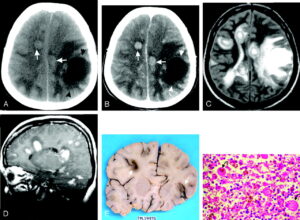

நோயின் ஆரம்ப அறிகுறிகளில் தலைவலி, காய்ச்சல், வாந்தி மற்றும் கழுத்து வலி போன்ற பொதுவான அறிகுறிகள் காணப்படுகின்றன. அறிகுறிகள் பொதுவான காய்ச்சல் அறிகுறிகளோடு ஒப்பிடும்போது, சரியான நேரத்தில் நோயை கண்டறிதல் சவாலாக இருக்கும்.